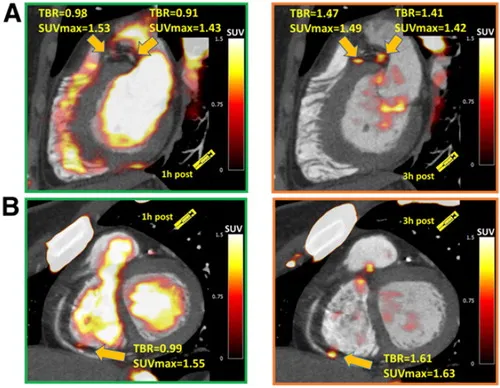

BJR publishes special feature on imaging patients with stable chest pain. BJR, the international research journal of the British Institute of Radiology, has published a collection of articles on the theme of imaging patients with stable chest pain, guest-edited by leading experts Professor Matthijs Oudkerk & Professor Edwin van Beek. Millions of people around the world suffer from chest pain. Diagnosing the cause of chest pain & identifying the level of risk are integral to the prevention of serious coronary events & poor patient outcomes. Imaging is central to these efforts & provides vital information to primary care physicians, cardiologists & the variety of doctors who manage patients with stable chest pain. Following the publication of the SCOT-HEART trial in 2015 (a study to see if coronary artery calcium score & computed tomography coronary angiogram alters the proportion of patients diagnosed with angina due to coronary heart disease), a new era of non-invasive coronary imaging has opened up. This BJR special feature covers many of the important topics & questions facing the scientists & clinicians working in the field & presents a collection of insightful Review articles & Commentaries from leading international experts. Professor Edwin van Beek said “This special feature is essential reading for any medical professionals interested in stable chest pain. The articles cover vital topics such as vulnerable plaque, cost-effectiveness for imaging stable ischemic disease, the potential for functional coronary & cardiac CT imaging, the role of machine learning, the role of MRI for the assessment of chest pain & the role of imaging in the evaluation of heart valve disease”. Professor Matthijs Oudkerk explains “This special feature marks the moment of publication of the first hard evidence that non-invasive coronary CT imaging in patients with chest pain saves lives compared to current medical practice & at the same time is a lot less harmful for the patient, costs less & is more effective. This special feature is not to be missed!”. You can access the special feature, here. Image Figure 1 from \"MRI perfusion in patients with stable chest-pain\" Images Figure 1 from "MRI perfusion in patients with stable chest-pain" Figure 1. The top row is an example of an ischemic perfusion defect, where the stress perfusion image shows a clear hypoperfused area (red arrows), whereas the LGE image shows no defect. The bottom row shows an infarct-related perfusion defect, where on both, stress perfusion (slightly hypoenhanced tissue, red arrows) and LGE image (strongly hyperenhanced tissue) a defect is shown (red arrows). This example of an infarct patient also demonstrates the superiority of LGE to delineate scar in comparison to the perfusion approach. In scar, the extracellular Gd-chelate contrast medium distributes in a large extracellular (fibrotic) compartment during first-pass, which increases the signal in the fibrotic tissue explaining its reduced sensitivity to detect hypoperfusion in scar. This reduced sensitivity to detect hypoperfusion is not observed in viable myocardium (with small extracellular compartment). LGE, late gadolinium enhancement. Image Figure 4 from \"Non-invasive imaging of high-risk coronary plaque: the role of computed tomography & positron emission tomography\" Figure 4 from "Non-invasive imaging of high-risk coronary plaque: the role of computed tomography & positron emission tomography" Figure 4. 18F-GP1 arterial uptake in right popliteal artery. 18F-GP1 PET-CT images of a patient who had recently undergone right common femoral artery endarterectomy & right popliteal artery angioplasty. Anterior maximum intensity projection & axial images taken 120 min after 18F-GP1 injection show focal increased uptake in the right popliteal artery (a, b); arrows), which corresponds to a thrombotic lesion after angioplasty (c). Additional 18F-GP1 uptake is seen in the dissected right distal external iliac artery (d, e); dotted arrows) & right common femoral artery (a, f); arrow heads) where endarterectomy was performed 3 days prior to the PET-CT (g, arrow head). Images courtesy of Chae et al.40 PET, positron emission tomography. Image Figure 5 from \"Vulnerable plaque imaging using 18F-sodium fluoride positron emission tomography\". Figure 5 from "Vulnerable plaque imaging using 18F-sodium fluoride positron emission tomography" Figure 5. Examples of coronary plaques with significant uptake on 3 h PET & low tracer activity of 1 h post injection imaging. Short axis images of proximal left anterior descending, proximal circumflex (A) & distal right coronary artery (B) plaques (arrows) which had a TBR <1.0 on 1 h PET (left column) & showed uptake exceeding the 1.25 TBR threshold at 3 h. This research was originally published in JNM. Kwiecinski J, Berman DS, Lee SE, Dey D, Cadet S, Lassen ML, Germano G, Jansen MA, Dweck MR, Newby DE, Chang HJ, Yun M, Slomka PJ. Three-Hour Delayed Imaging Improves Assessment of Coronary 18F-Sodium Fluoride PET. J Nucl Med. 2019 Apr;6025 :530–535. doi: 10.2967/jnumed.118.217885. PET, positron emission tomography; SUV, standardized uptake value; TBR, target to background ratio. Related links British Institute of Radiology British Journal of Radiology British Journal of Radiology special feature Professor Edwin van Beek Professor David Newby Professor Marc Dweck SCOT-HEART What is a CT scan? What is a PET scan? What is a MR scan? What is a PET-CT scan? "MRI perfusion in patients with stable chest-pain" "Non-invasive imaging of high-risk coronary plaque: the role of computed tomography & positron emission tomography" "Vulnerable plaque imaging using 18F-sodium fluoride positron emission tomography" Social media tags & titles BJR publishes special feature on imaging patients with stable chest pain. @BIR_News @BJR_Radiology @SINAPSECENTRE @MarcDweck #ChestPain Publication date 16 Sep, 2020